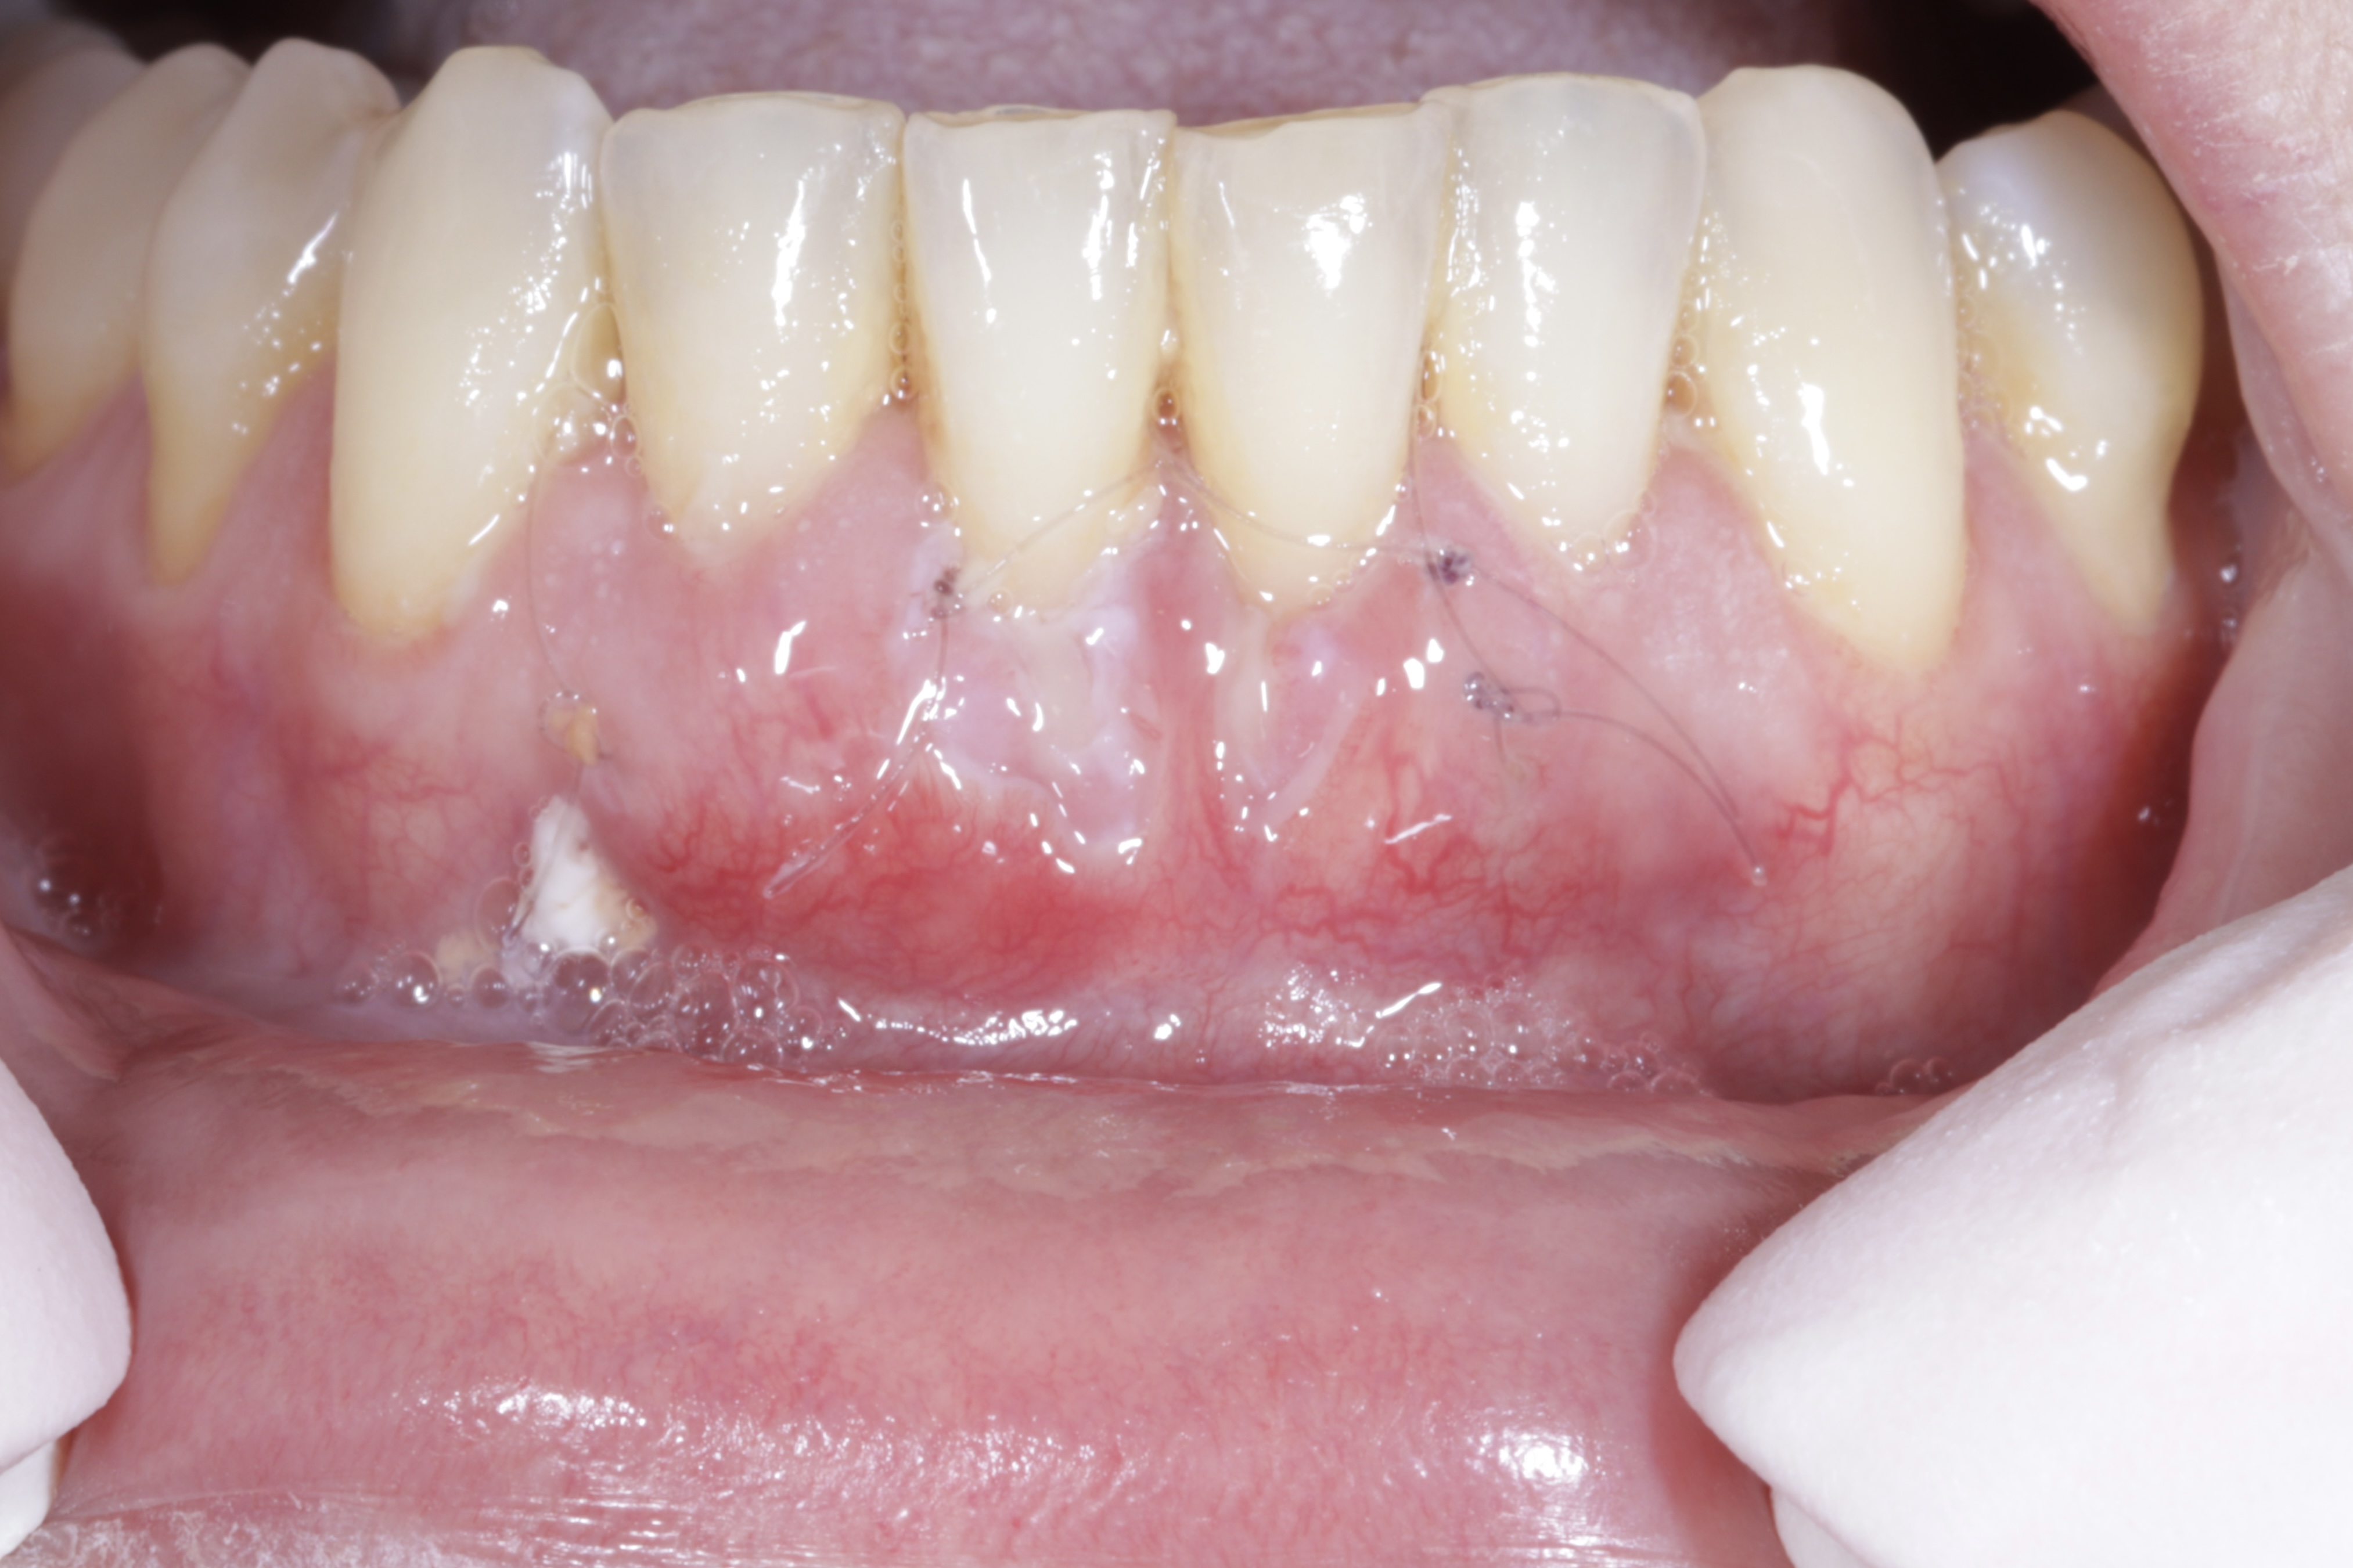

Podrás asistir a la planificación de casos y cirugía de injerto de tejido conectivo. Factores determinantes y elección de la técnica adecuada. Sumérgete en un protocolo predecible y técnicamente correcto para obtener resultados óptimos.

Ofrecemos una inmersión pura en una de nuestras pasiones, la Regeneración Periodontal, tanto para niveles iniciales como avanzados. En este modelo de estancia clínica ofrecemos una parte teórica, presentación de casos clínicos, un taller hands-on y a convenir, la asistencia a una cirugía

Formación teórico-práctica completa sobre las técnicas más avanzadas en cirugía mucogingival. Durante dos días intensivos, los participantes aprenderán desde la evidencia científica y la anatomía de las zonas donantes hasta la ejecución de injertos, cubrimiento radicular y aumento de